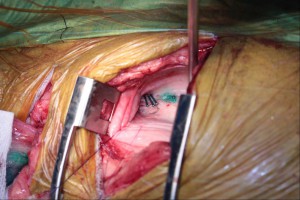

術中の写真(1回目)

画面の上が頭側です。右第9肋間から開胸し開胸器にて術野を確保しているところです。白濁の乳びが多量に貯留していました。

インドシニアグリーン色素にて腸間膜リンパ節を介して胸管を可視化している最中です。

大動脈直上の縦隔胸膜を切開し胸管へのアプローチの準備をしているところです。

吸引器の左に3本緑に染まった胸管が確認されます

チタンクリップにて胸管を2箇所結紮したところです